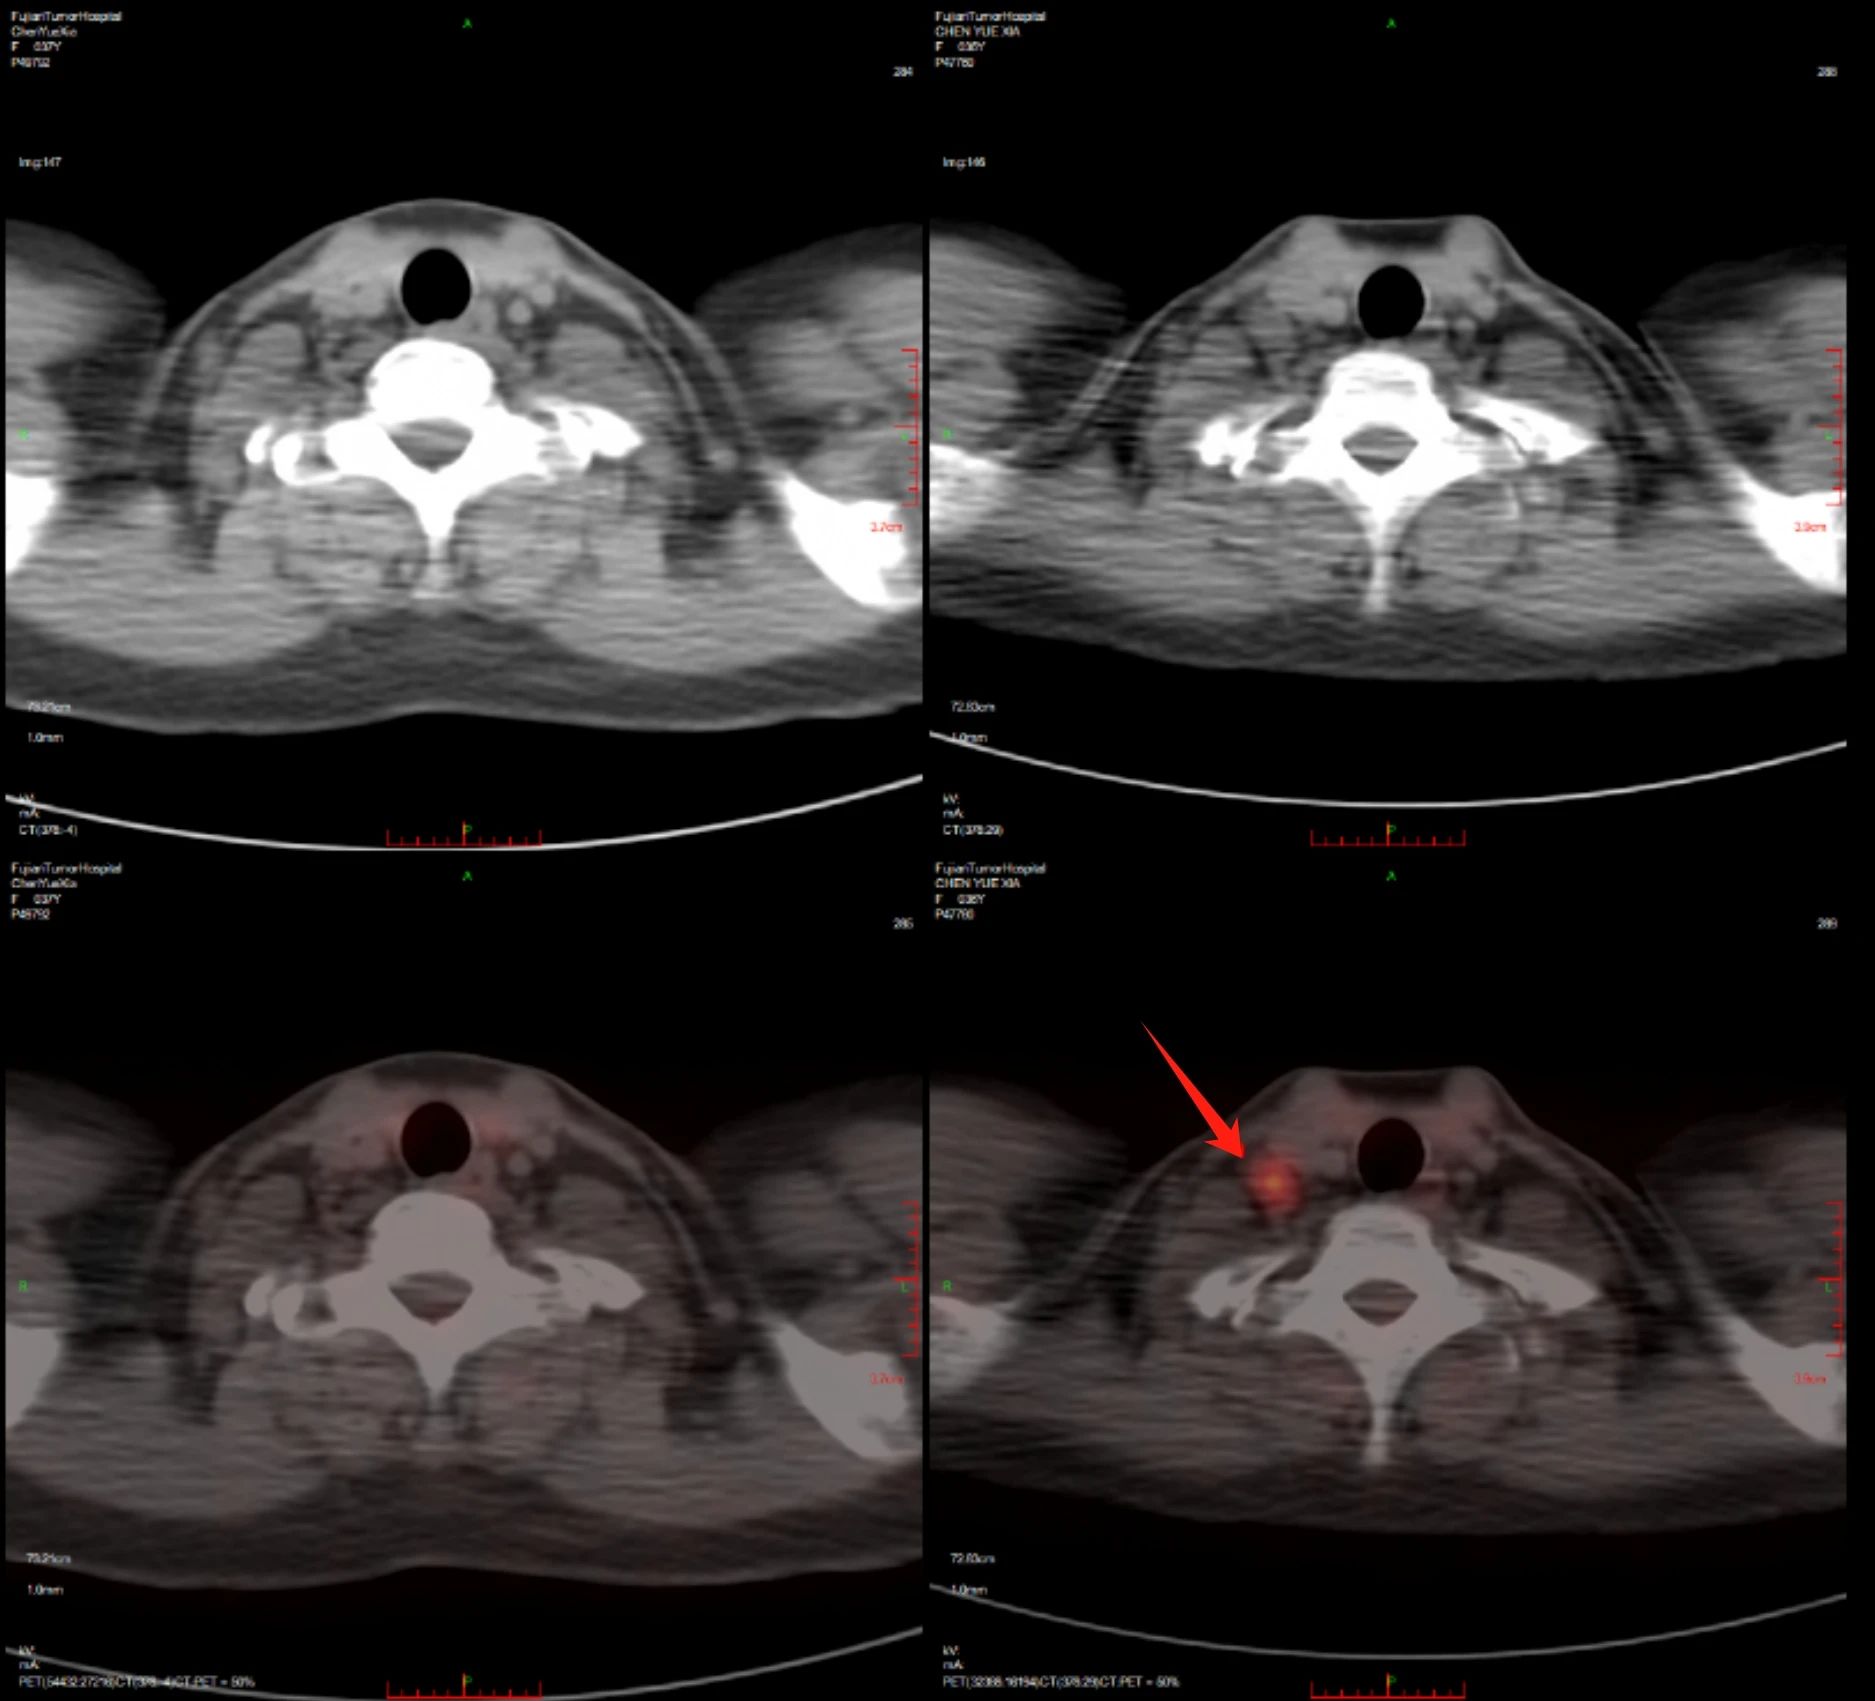

治疗后

治疗前

明确诊断后,团队仔细钻研病情,同时大量查阅最新文献指南。先是尝试免疫加靶向治疗(PD1单抗联合维布妥昔单抗),后又启用维布妥昔单抗联合苯达莫司汀方案,四个周期后患者达到完全缓解。接着,团队为患者实施自体干细胞移植治疗,并参考前沿文献开展靶向维持以巩固效果。近期随访显示,患者仍处于完全缓解状态,病情得到长期有效管控。